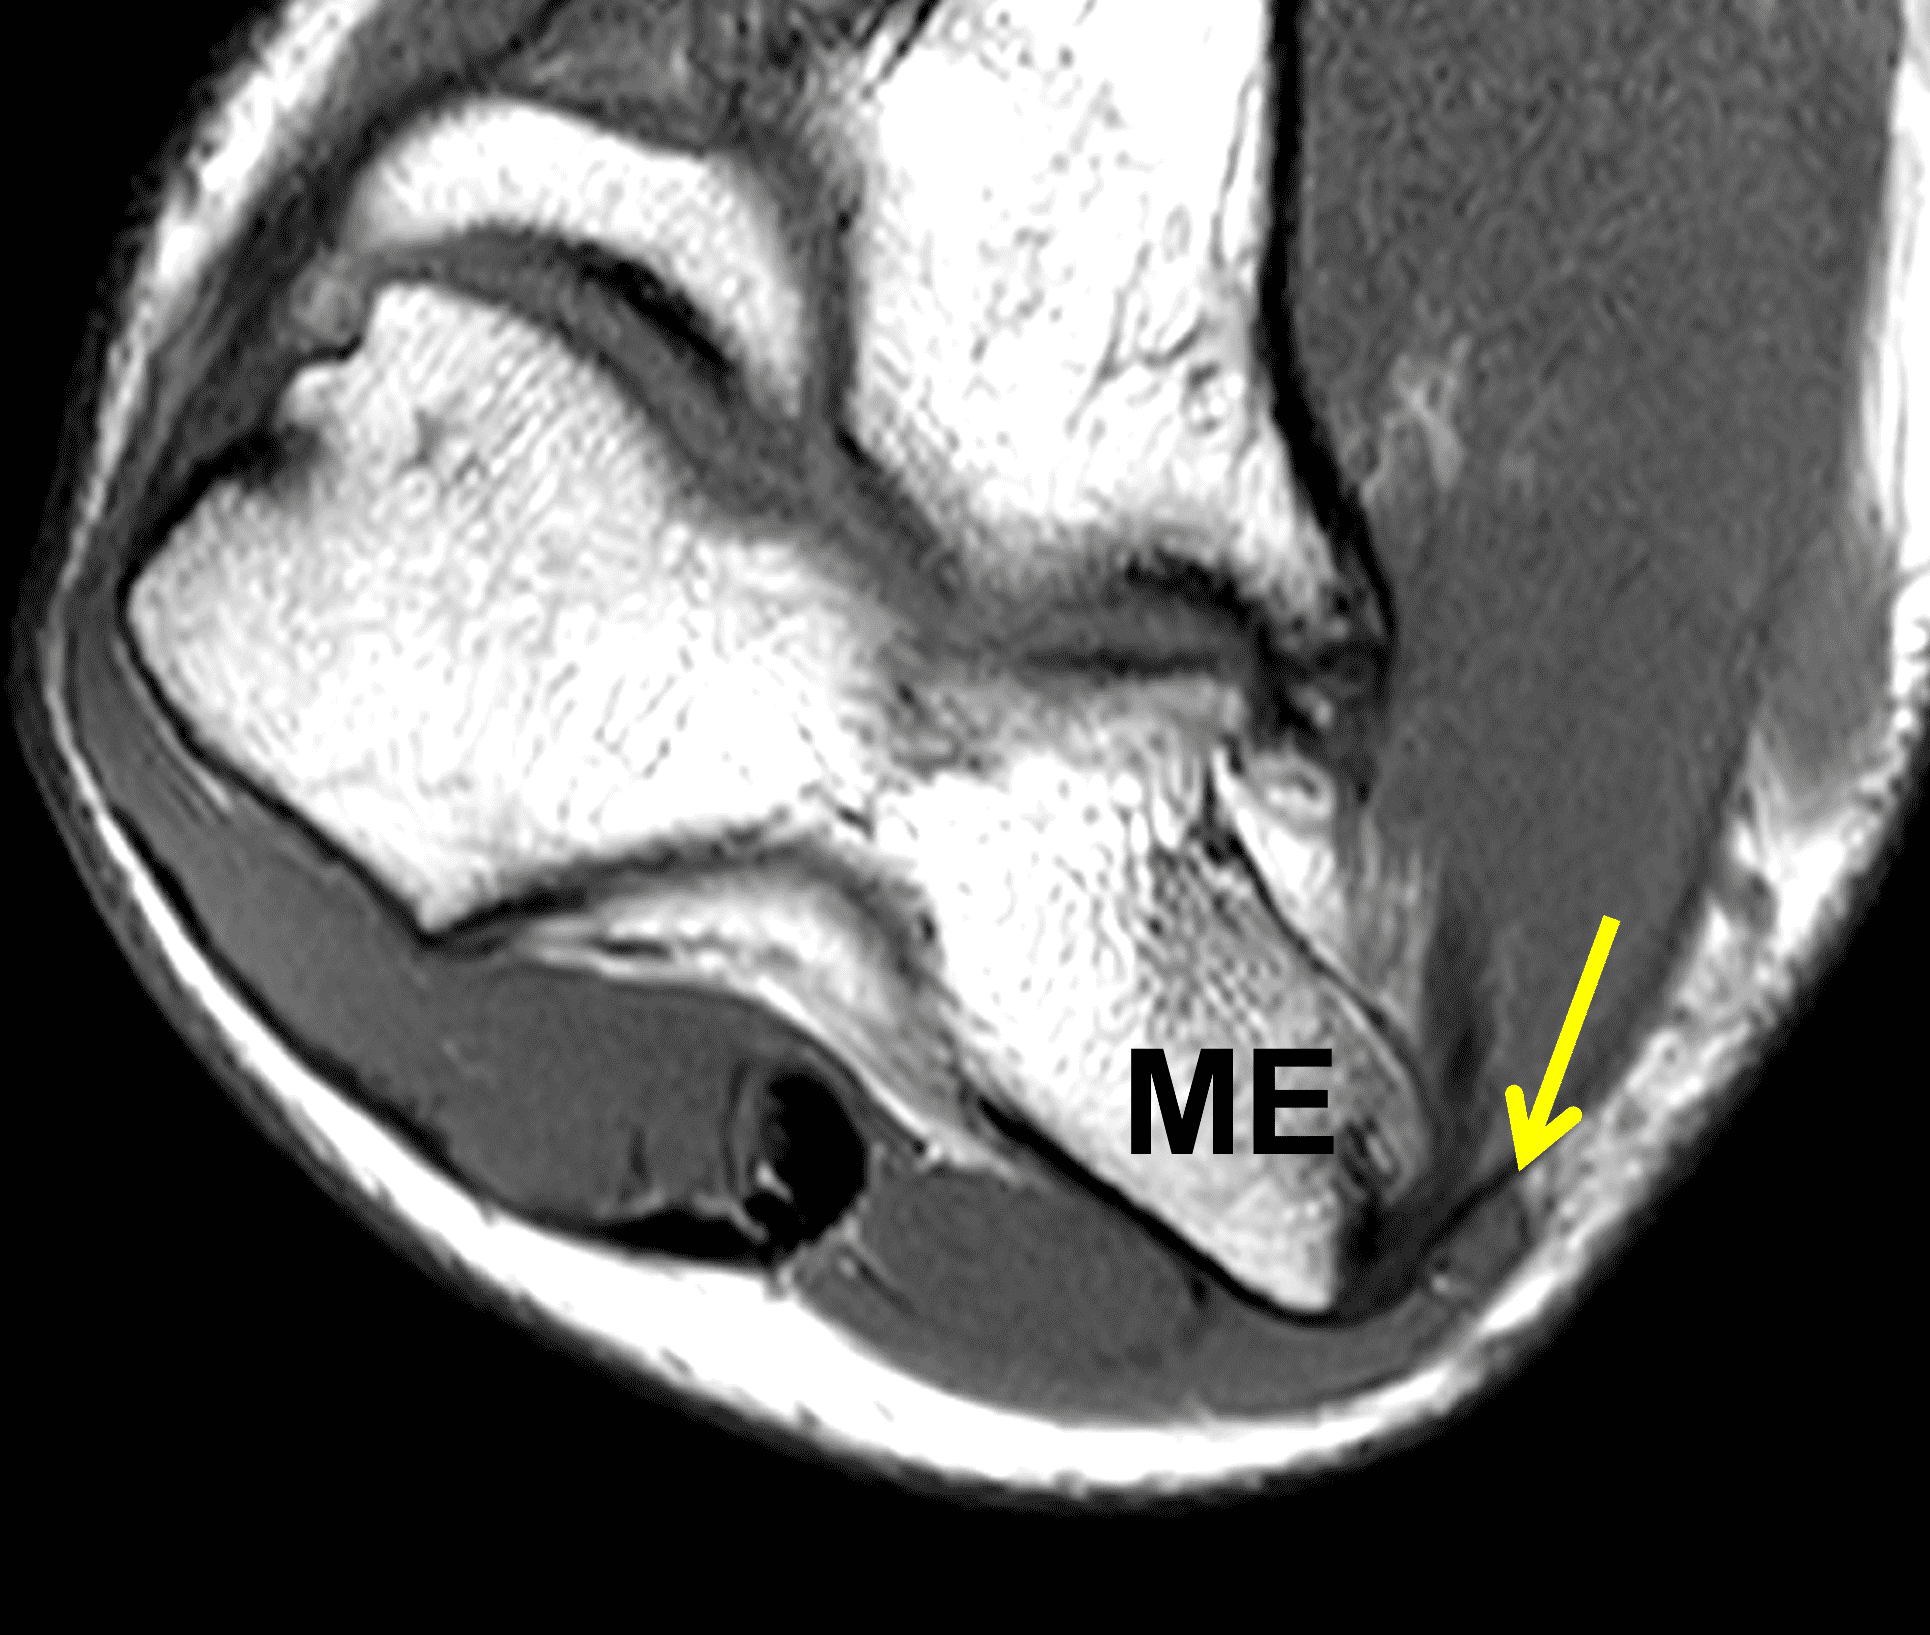

Figure 7: Absent cubital tunnel retinaculum. (7A) Drawing depicts absence of the retinaculum overlying the cubital tunnel contents. Compare with Figure 3B. (7B) Axial T1-weighted image with the elbow extended shows a normally-positioned ulnar nerve (arrow) with no defined retinaculum extending from the olecranon to the medial epicondyle. In the same patient with the elbow flexed, (7C) T1-weighted and (7D) fat-suppressed, fluid-sensitive images demonstrate dislocation of the ulnar nerve (arrows) relative to the medial epicondyle (ME).